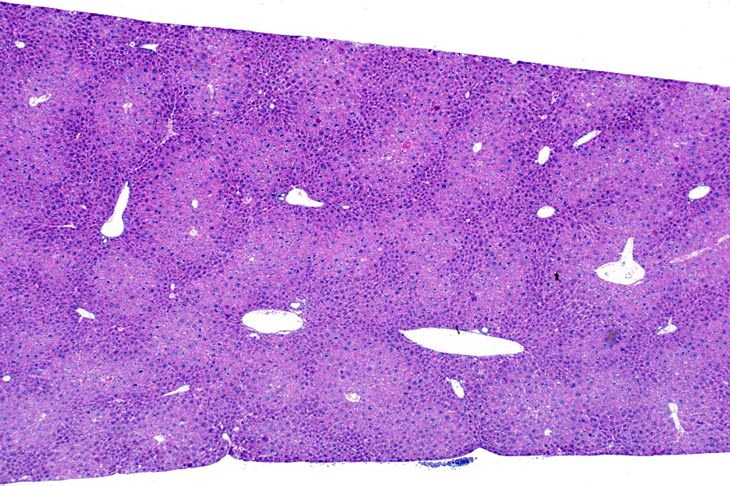

Centrilobular hepatocellular hypertrophy in a CD-1 mouse.